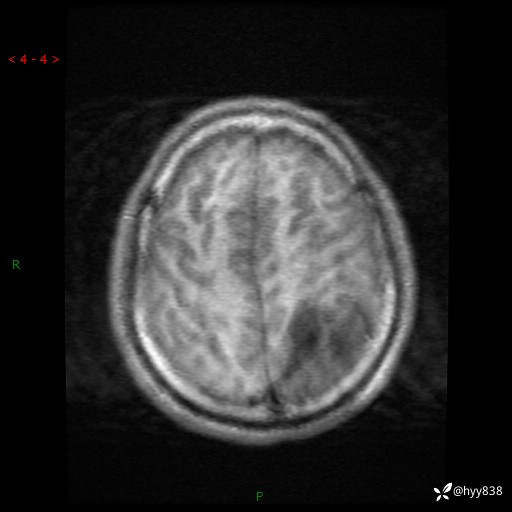

病例年轻小伙,头痛伴呕吐半年,渐进性加重1月。疑难病例,第一次见--结果公布~

性别:男

年龄:21岁

简要病史:头痛伴呕吐半年,渐进性加重1月

颅脑MRI平扫+增强